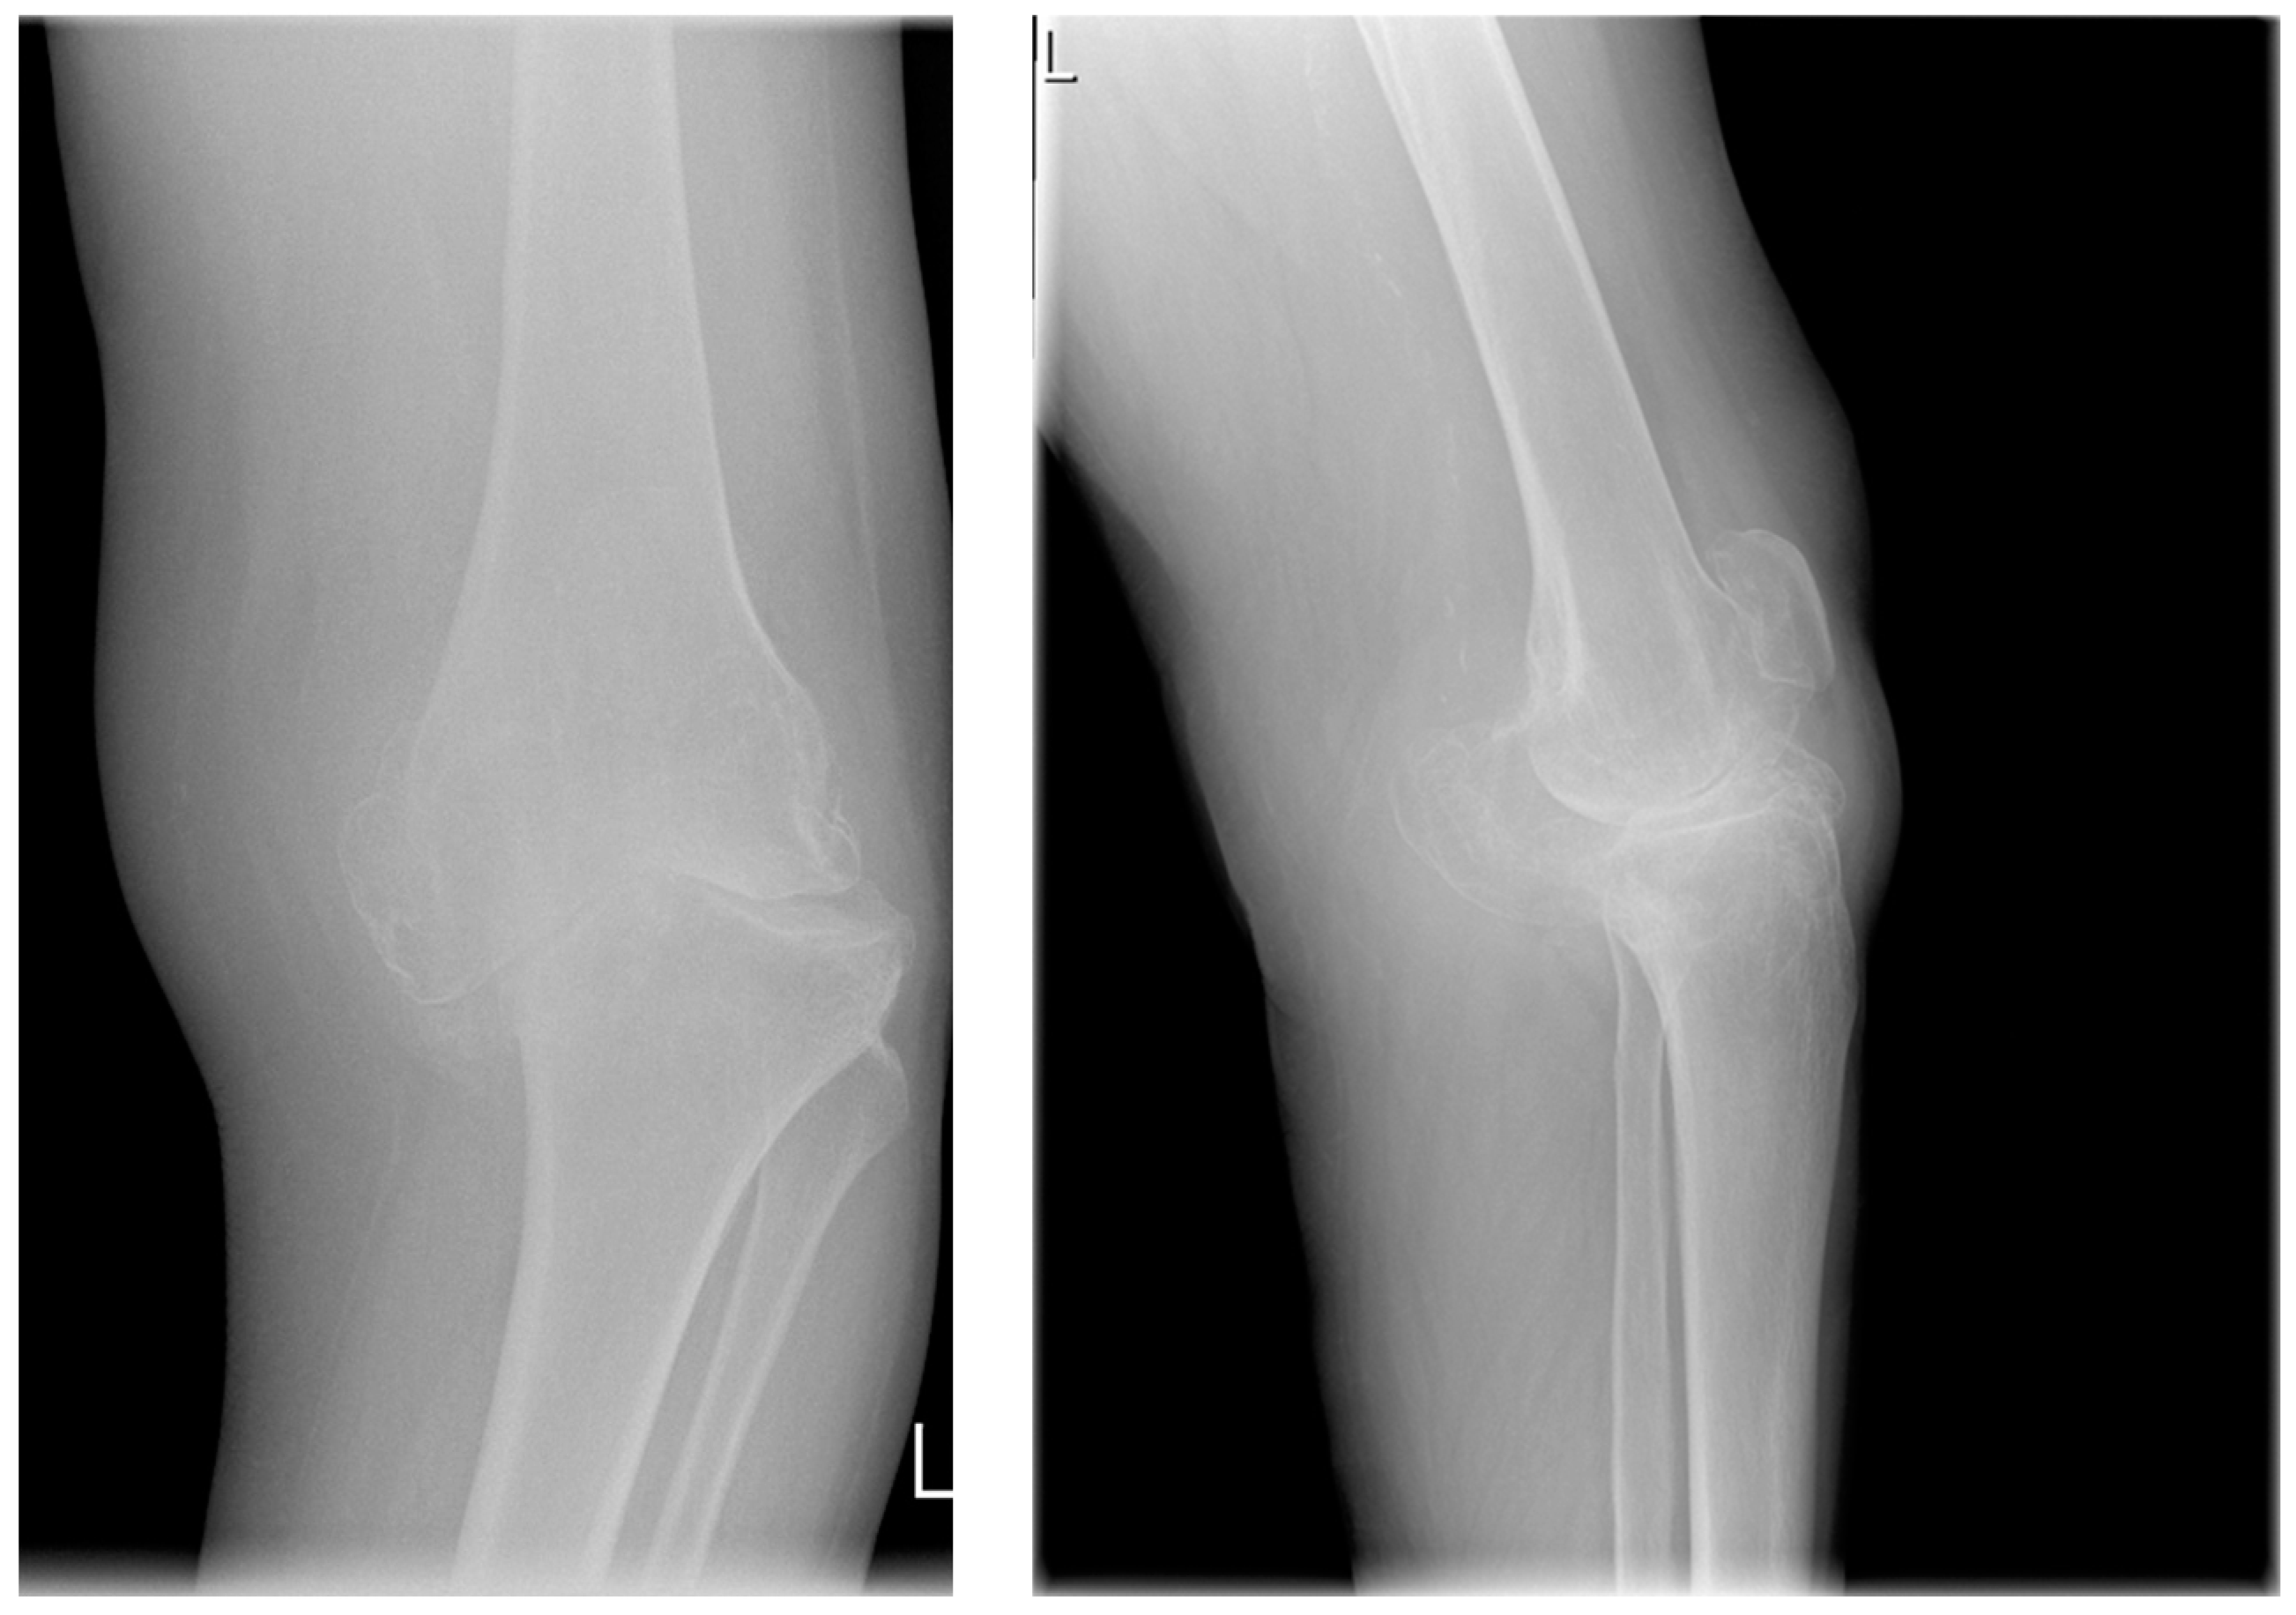

Primary knee osteoarthritis is the destruction of articular cartilage in conjunction with excessive thickening of the subchondral bone layer, the formation of osteophytes, and the deformation of the affected joint (Figure 1) [2]. Primary osteoarthritis affects the medial tibiofemoral compartment in over 95% of cases. However, despite the known clinical course of the disease, the etiology and risk factors in primary osteoarthritis have not been fully elucidated [3].

Figure 1. Osteoarthritis of the knee joint; in the upper part of the figure, femoral condyles are seen with major osteoarthritic changes. In the lower part, the tibial plateau (partially) is seen. Source: proprietary material, intraoperative photograph.